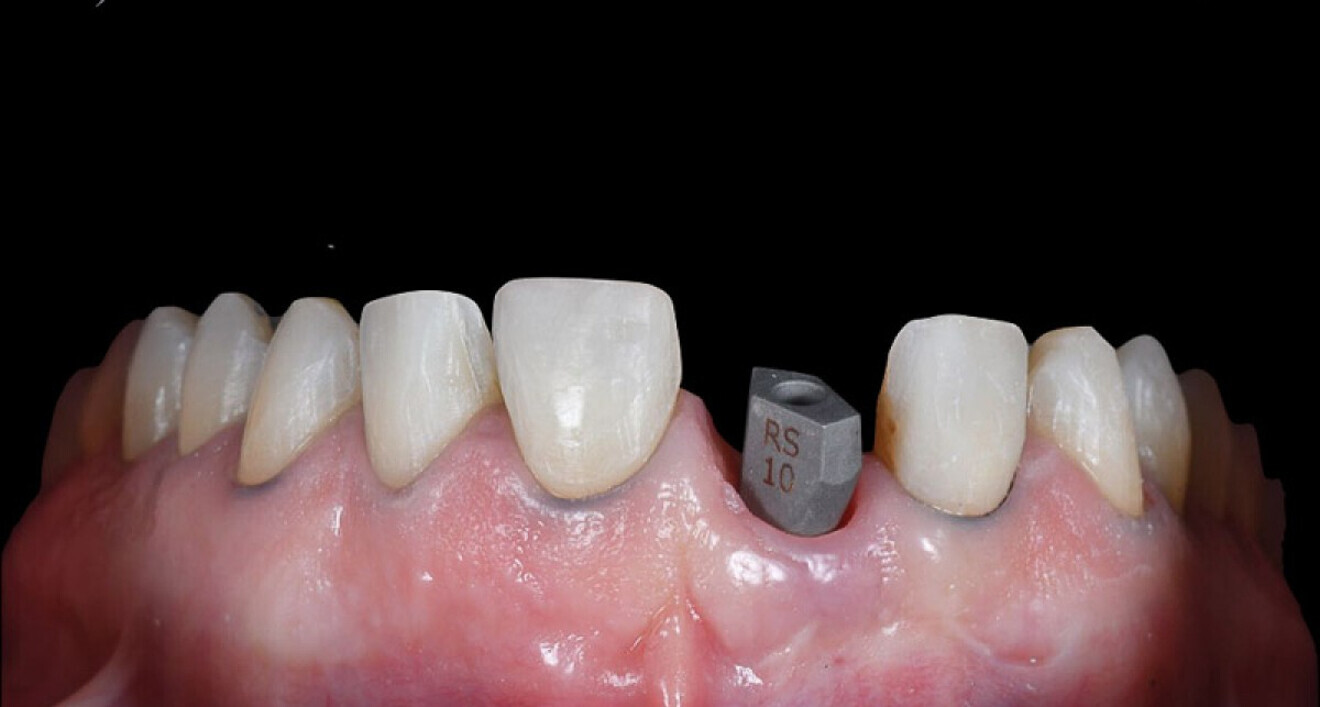

De 39-jarige patiënt kwam bij ons met het verzoek om zijn glimlach te verbeteren. De eerste esthetische analyse bracht het volgende aan het licht:

• disproportionele spacing;

• aanwezigheid van diasteem;

• verkeerde inclinatie van de tandassen;

• te veel ruimte tussen de buccale vlakken van de elementen in de bovenkaak en de mondhoeken (afb. 1, 2).

Afb. 1